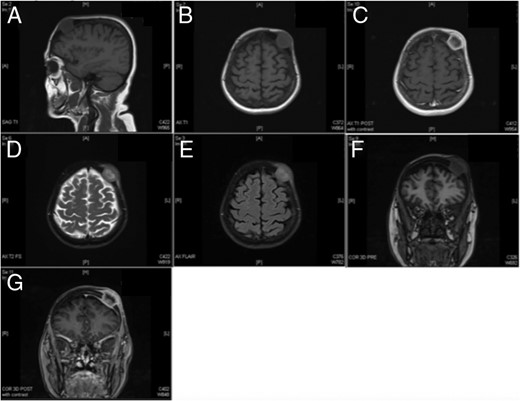

The patient, a 69-year-old white female, was referred by her primary care provider to a plastic surgeon at United Hospital Center for treatment of what was believed to be a soft-tissue mass of the left forehead (frontoparietal region) (Fig. 1). The mass had increased in size for the prior 2–3 months and resulted in a radiating pain down the left side of the face. The mass was non-mobile and tender to touch. Prior to this referral, the patient was relatively healthy with a past medical history significant for arthritis, depression and hypertension. Her surgical history was positive for tonsillectomy and partial hysterectomy. Her social history is significant for a 60-pack-year smoking history (1.5 packs/day for 40 years). The soft tissue mass had been managed conservatively for presumptive dermatological infection (subcutaneous/sebaceous cyst) with a 10-day course of levofloxacin 500 mg tablets taken once daily. The tablets, however, provided no symptomatic relief. Imaging (computed tomography (CT)) of the maxillofacial area and brain without contrast was obtained in addition to plain films of the skull. These images revealed a lytic lesion of the skull in the left frontopartietal region (Fig. 2). The patient was referred to the oncology department for further workup.

Schematic representation of the lesion location. The soft-tissue component was measured at a diameter of 3.3 cm and located on the left forehead near the hairline.